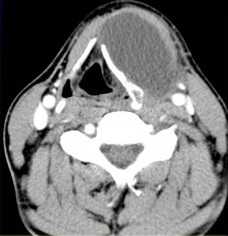

(Слева) УЗИ, поперечная проекция: визуализируется веретенообразная гипоэхогенная опухоль В и нижней трети шеи слева (известная локализация ПС). Обратите внимание на связь с корешками/ветвями ПС. На УЗИ в продольной плоскости (не показана) также определяется связь опухоли с плечевым сплетением - это подозрительный признак шванномы ПС.

(Справа) MPT (Т2 ВИ FS), аксиальная проекция: визуализируется шваннома ПС, связанная с корешком. УЗИ позволяет идентифицировать опухоль и отличить ее от лимфоузлов, чаще встречающихся в этой области. (Слева) УЗИ, поперечная проекция: визуализируется солидная гипоэхогенная опухоль с задним усилением, лежащая между передней и средней лестничными мышцами. Расположение в перивертебральном пространстве и УЗ-картина являются диагностическими признаками шванномы ПС.